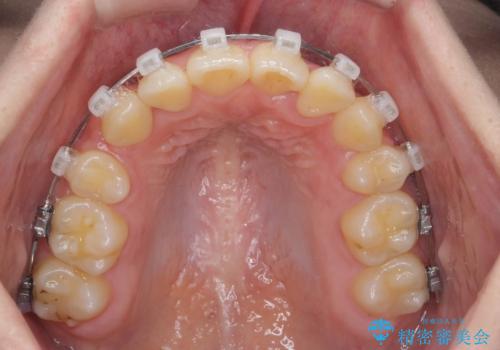

歯並びのせいで歯ブラシがしづらい マルチブラケットを用いた抜歯矯正

- 歯並びのがたつきにより歯ブラシがしづらく、今後虫歯になってしまう不安から、矯正治療を希望されて来院されました。

歯を並べるにはスペースが不足しているため、小臼歯の抜歯を4本行うマルチブラケット矯正による治療を計画します。

治療後は非常に歯ブラシがしやすくなったと、治療結果に満足いただくことができました。